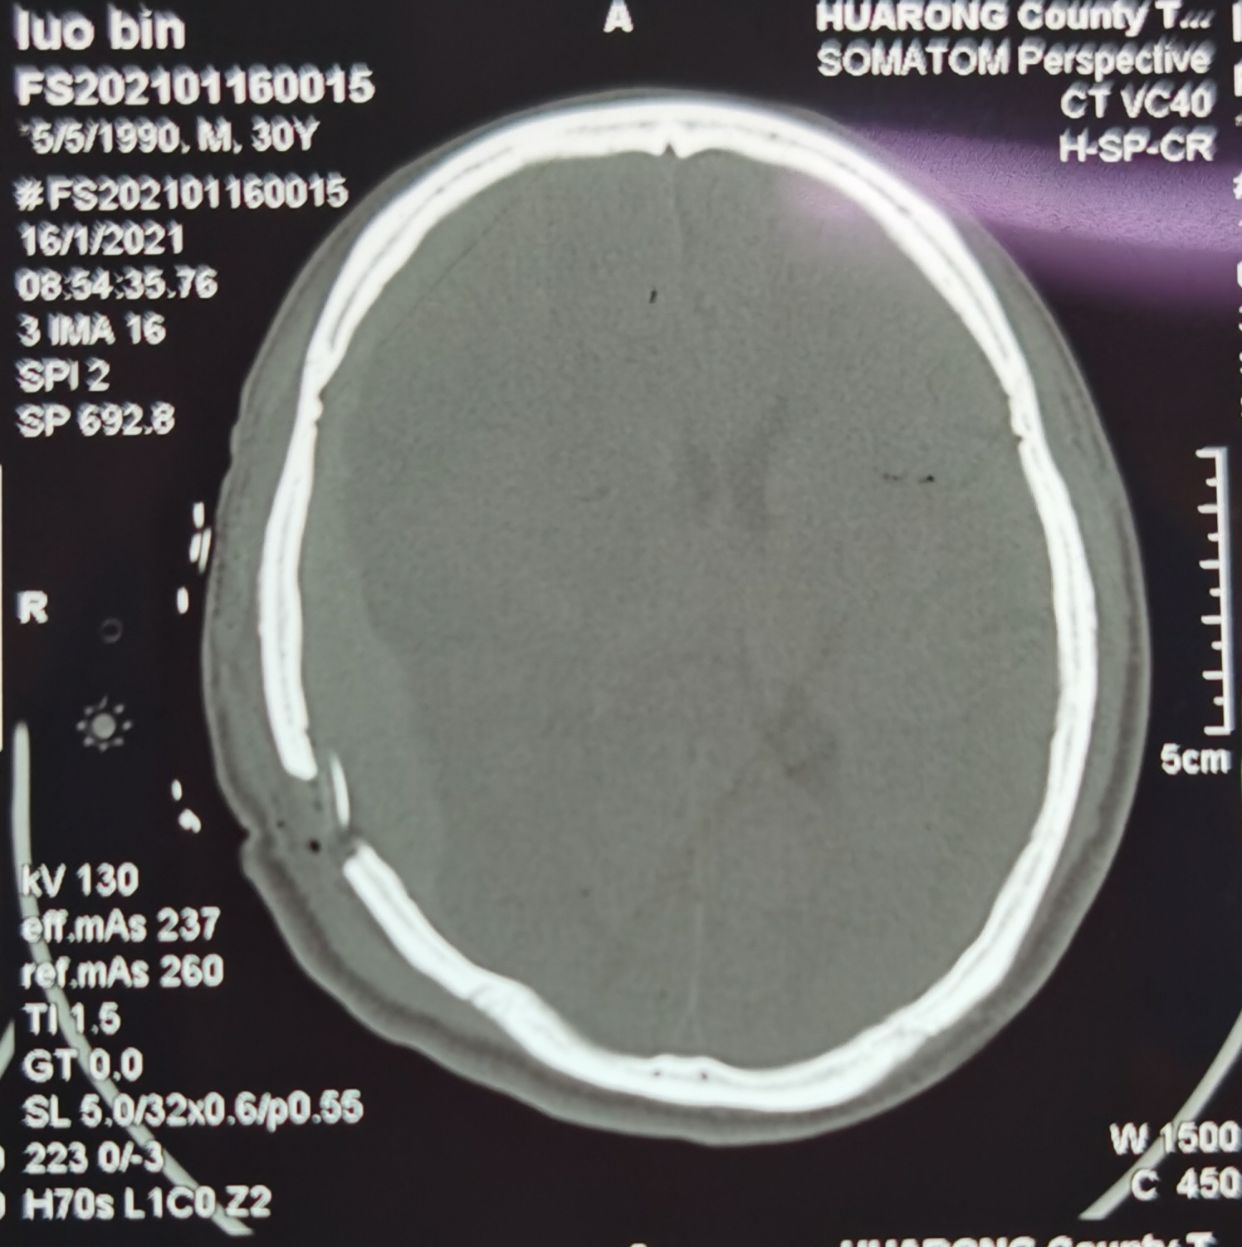

术后复查CT如下,进一步确认了此为硬膜下血肿,不是硬膜外血肿!

术后予以尿激酶液化,引流效果理想,患者无特殊不适。

1月19号复查CT,硬膜下血肿显著减少!